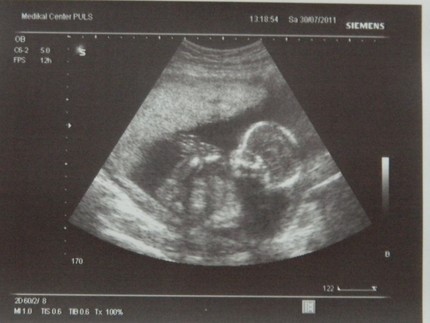

Узи 9 месяц

Узи 9 месяц 112 фотографий